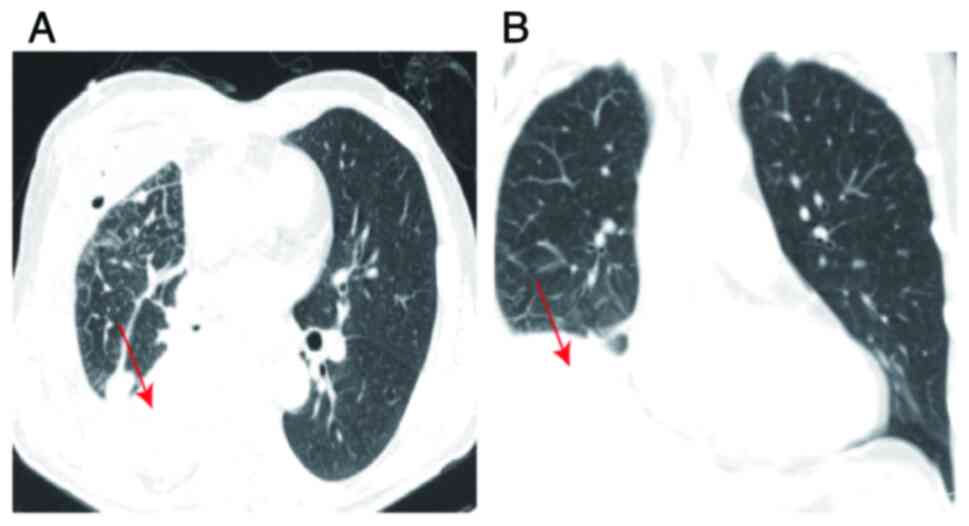

In clinical practice, the management of a lung abscess (LA) usually initiates with antibiotic administration to address the infection. Nevertheless, for cases presenting with refractory pulmonary tumors complicated by a LA, surgical intervention stands as an essential therapeutic recourse. The current study presents case involving lung cancer complicated by a LA. Despite continuously elevated infection marker levels, surgical intervention was promptly performed following the normalization of the patient's temperature. Subsequent postoperative histopathological analysis and immunohistochemistry revealed a moderately differentiated squamous cell carcinoma located in the lower right lung, classified as T2aN0M0, Ib stage. Following a 2‑year follow‑up period, no cancer recurrence was observed and the patient exhibited a favorable prognosis. This case highlights the vital role of surgical timing in the management of lung cancer complicated by an acute LA. Early surgical intervention may play a crucial role in arresting the advancement of lung cancer, indicating that prompt surgery upon temperature normalization could serve as a significant treatment indication for these patients.

Figure 1